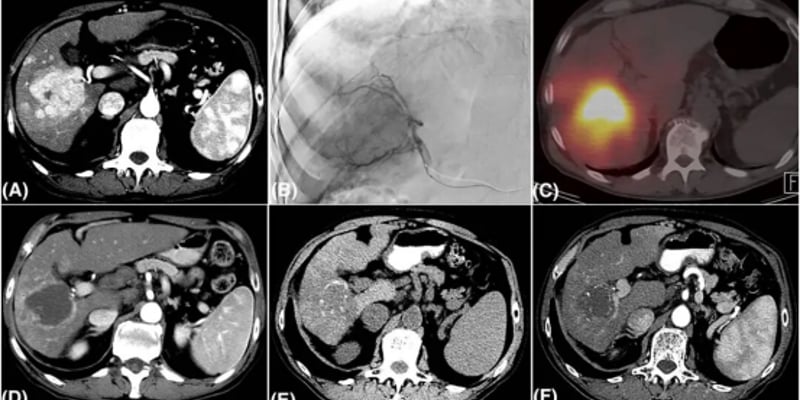

- 局部放疗与免疫疗法联用: 目前的研究表明,局部放疗与免疫疗法联用时可产生协同效应。放疗不仅能直接杀伤肿瘤细胞,还能诱导肿瘤释放更多的肿瘤抗原,刺激免疫反应,从而提升全身的抗肿瘤免疫,甚至可能引发未照射病灶的缩小,这种现象被称为“远隔效应”。一项替西木单抗联合微波消融的研究结果显示,治疗后患者血液循环中活化的CD8+T细胞数量增加,T细胞克隆重排多样性也有增加趋势,这表明全身免疫被激活,提示了“远隔效应”的潜在机制。